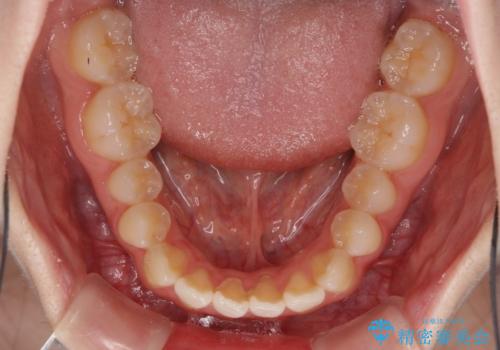

- 前歯の捻れと、ちょっとした出っ張りを気にして来院された患者様です。

歯と歯の間を削る(IPR)ことでデコボコを解消し、インビザラインで整えることとしました。

インビザライン治療特有の奥歯が接触しない時期が続き、当初予定よりも期間がかかりましたが、最終的には安定した咬み合わせと、整った前歯になりました。